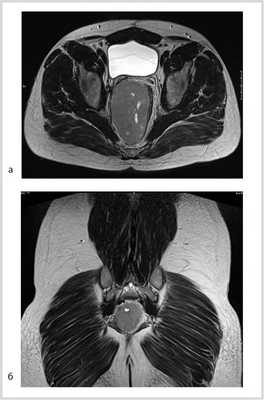

По данным магнитно-резонансной томографии (МРТ) от 10.02.2012, в полости малого таза пресакрально располагается опухоль размером 9,2×9×7 см. Верхний полюс ее на уровне тела S I позвонка, распространяется в параректальную клетчатку, тесно прилежит к прямой кишке, оттесняя ее влево (граница прослеживается). Нельзя исключить прорастание в кишку, стенки прямой кишки отечны. Опухоль прилежит к семенным пузырькам и предстательной железе (граница прослеживается); мочевой пузырь оттеснен кпереди и кверху; верхний полюс опухоли расположен между грушевидными мышцами, прилежит к передней поверхности крестца и копчика (граница прослеживается), нижний полюс опухоли расположен между волокнами мышцы, поднимающей задний проход; нижние ягодичные сосуды справа оттеснены кпереди, тесно прилежат к опухоли на протяжении 3 см (рис. 2).

Рис. 2. МР-томограммы малого таза. Пресакрально располагается опухоль размером 9,2×9×7 см. а — сагиттальный срез; б — фронтальный срез.